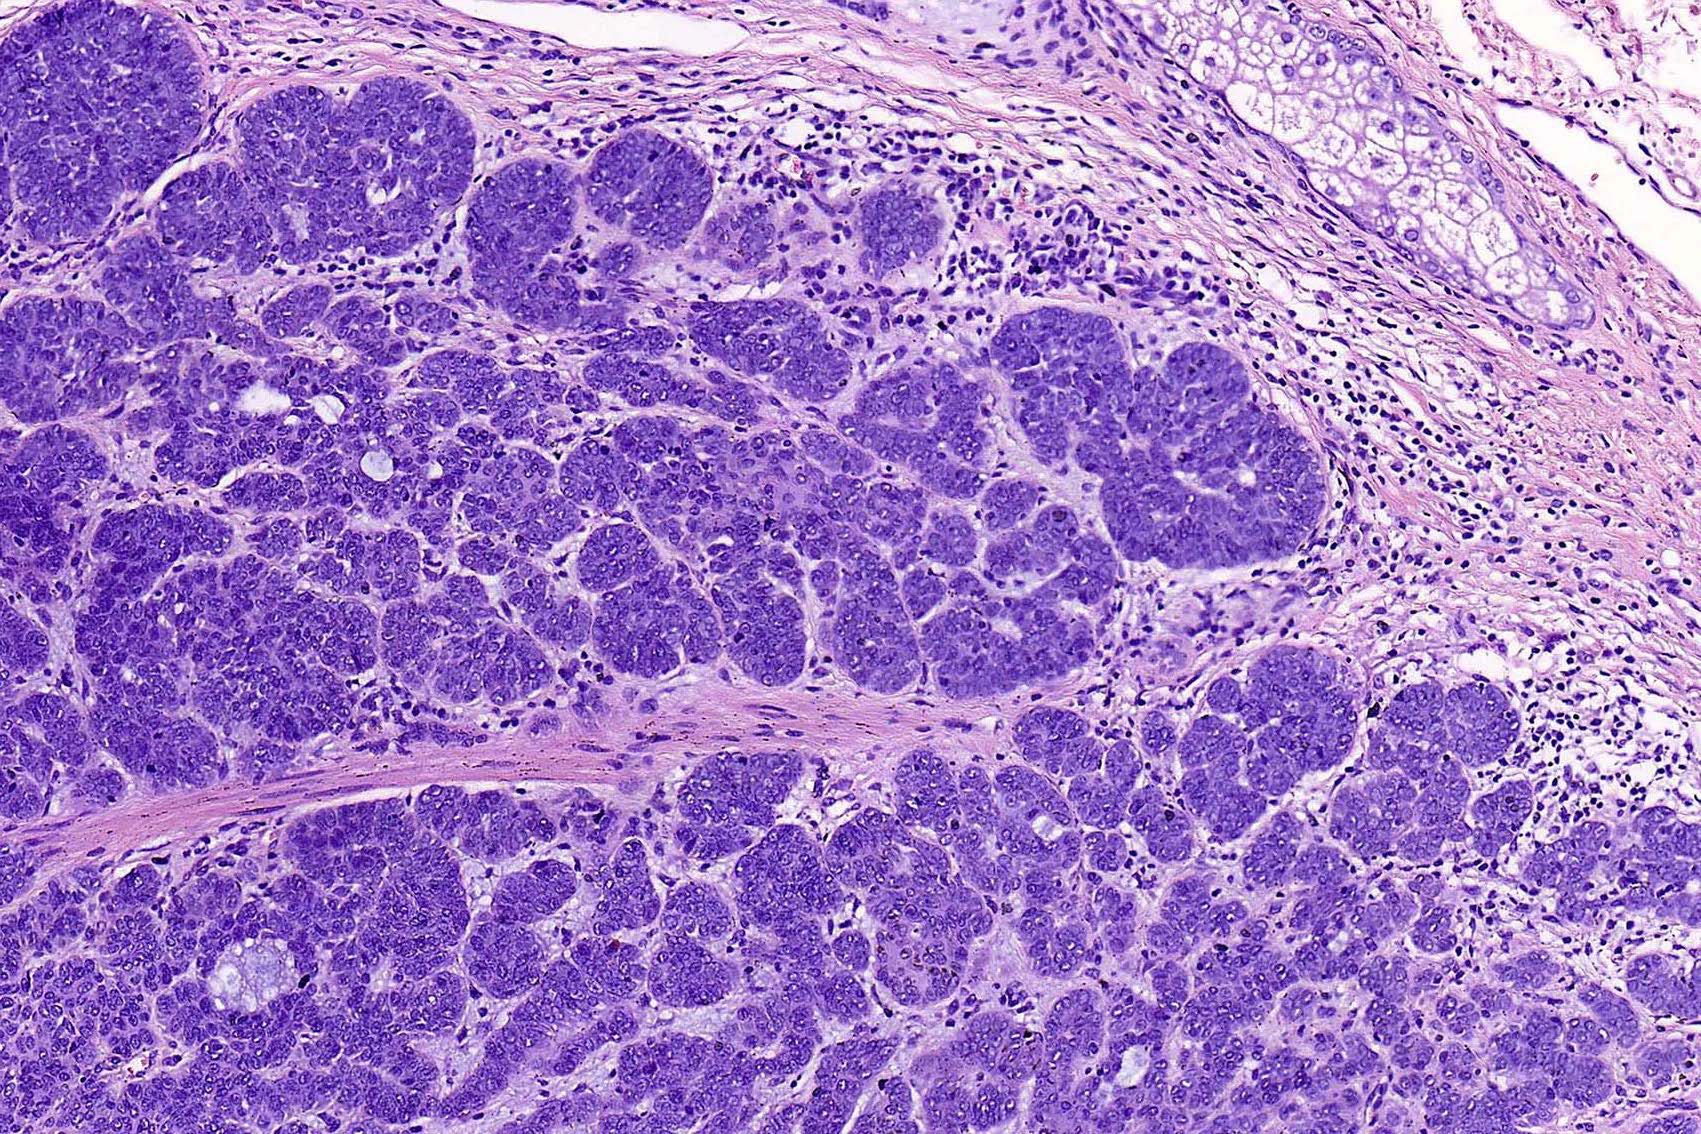

- Nodular and nodulocystic BCC

- Relatively circumscribed mass

- Epidermal or follicular attachment variably present

- Large basaloid lobules with peripheral nuclear palisade

- Lobules may be solid or show central cyst formation due to excessive mucin production

- Fibromyxoid stroma

- Cleft formation between tumor lobules and stroma

- Pleomorphism is generally mild

- Variable mitotic activity and apoptosis

- Sometimes necrosis en masse